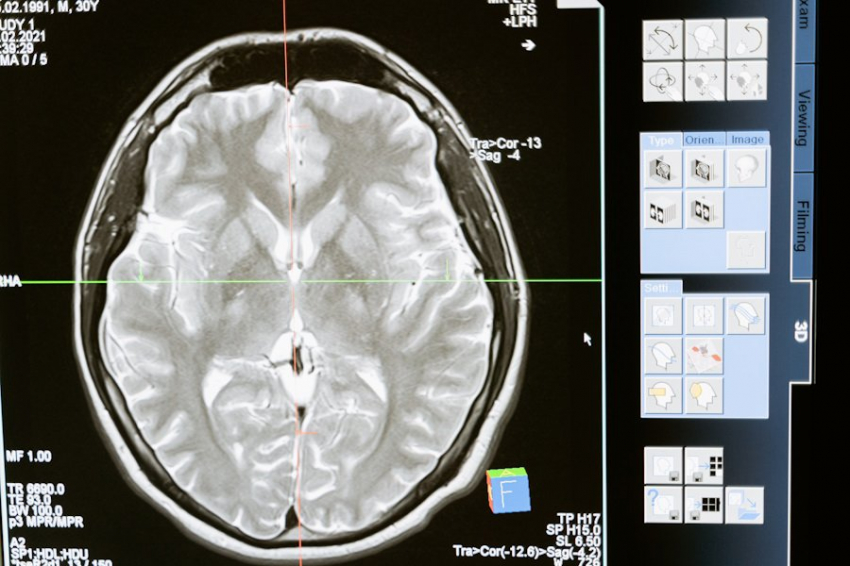

Фото из открытых источников Согласно новому исследованию, проведенному учеными из Weill Cornell Medicine, новая доклиническая модель предлагает уникальную платформу для изучения процесса болезни Паркинсона и предлагает относительно простой метод выявления заболевания у людей. В исследовании, опубликованном...